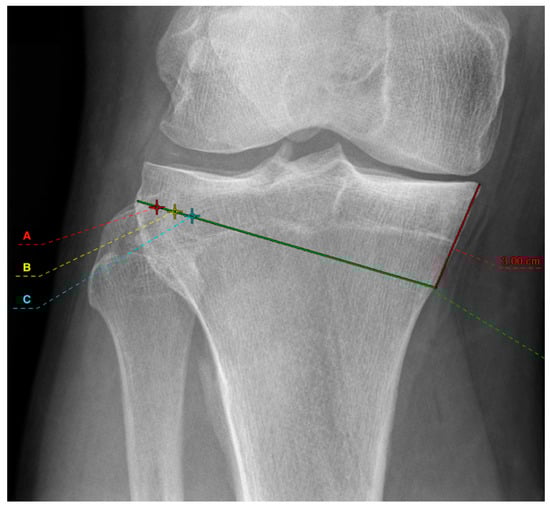

2. Materials and Methods

2.1. Radiographic Assessment